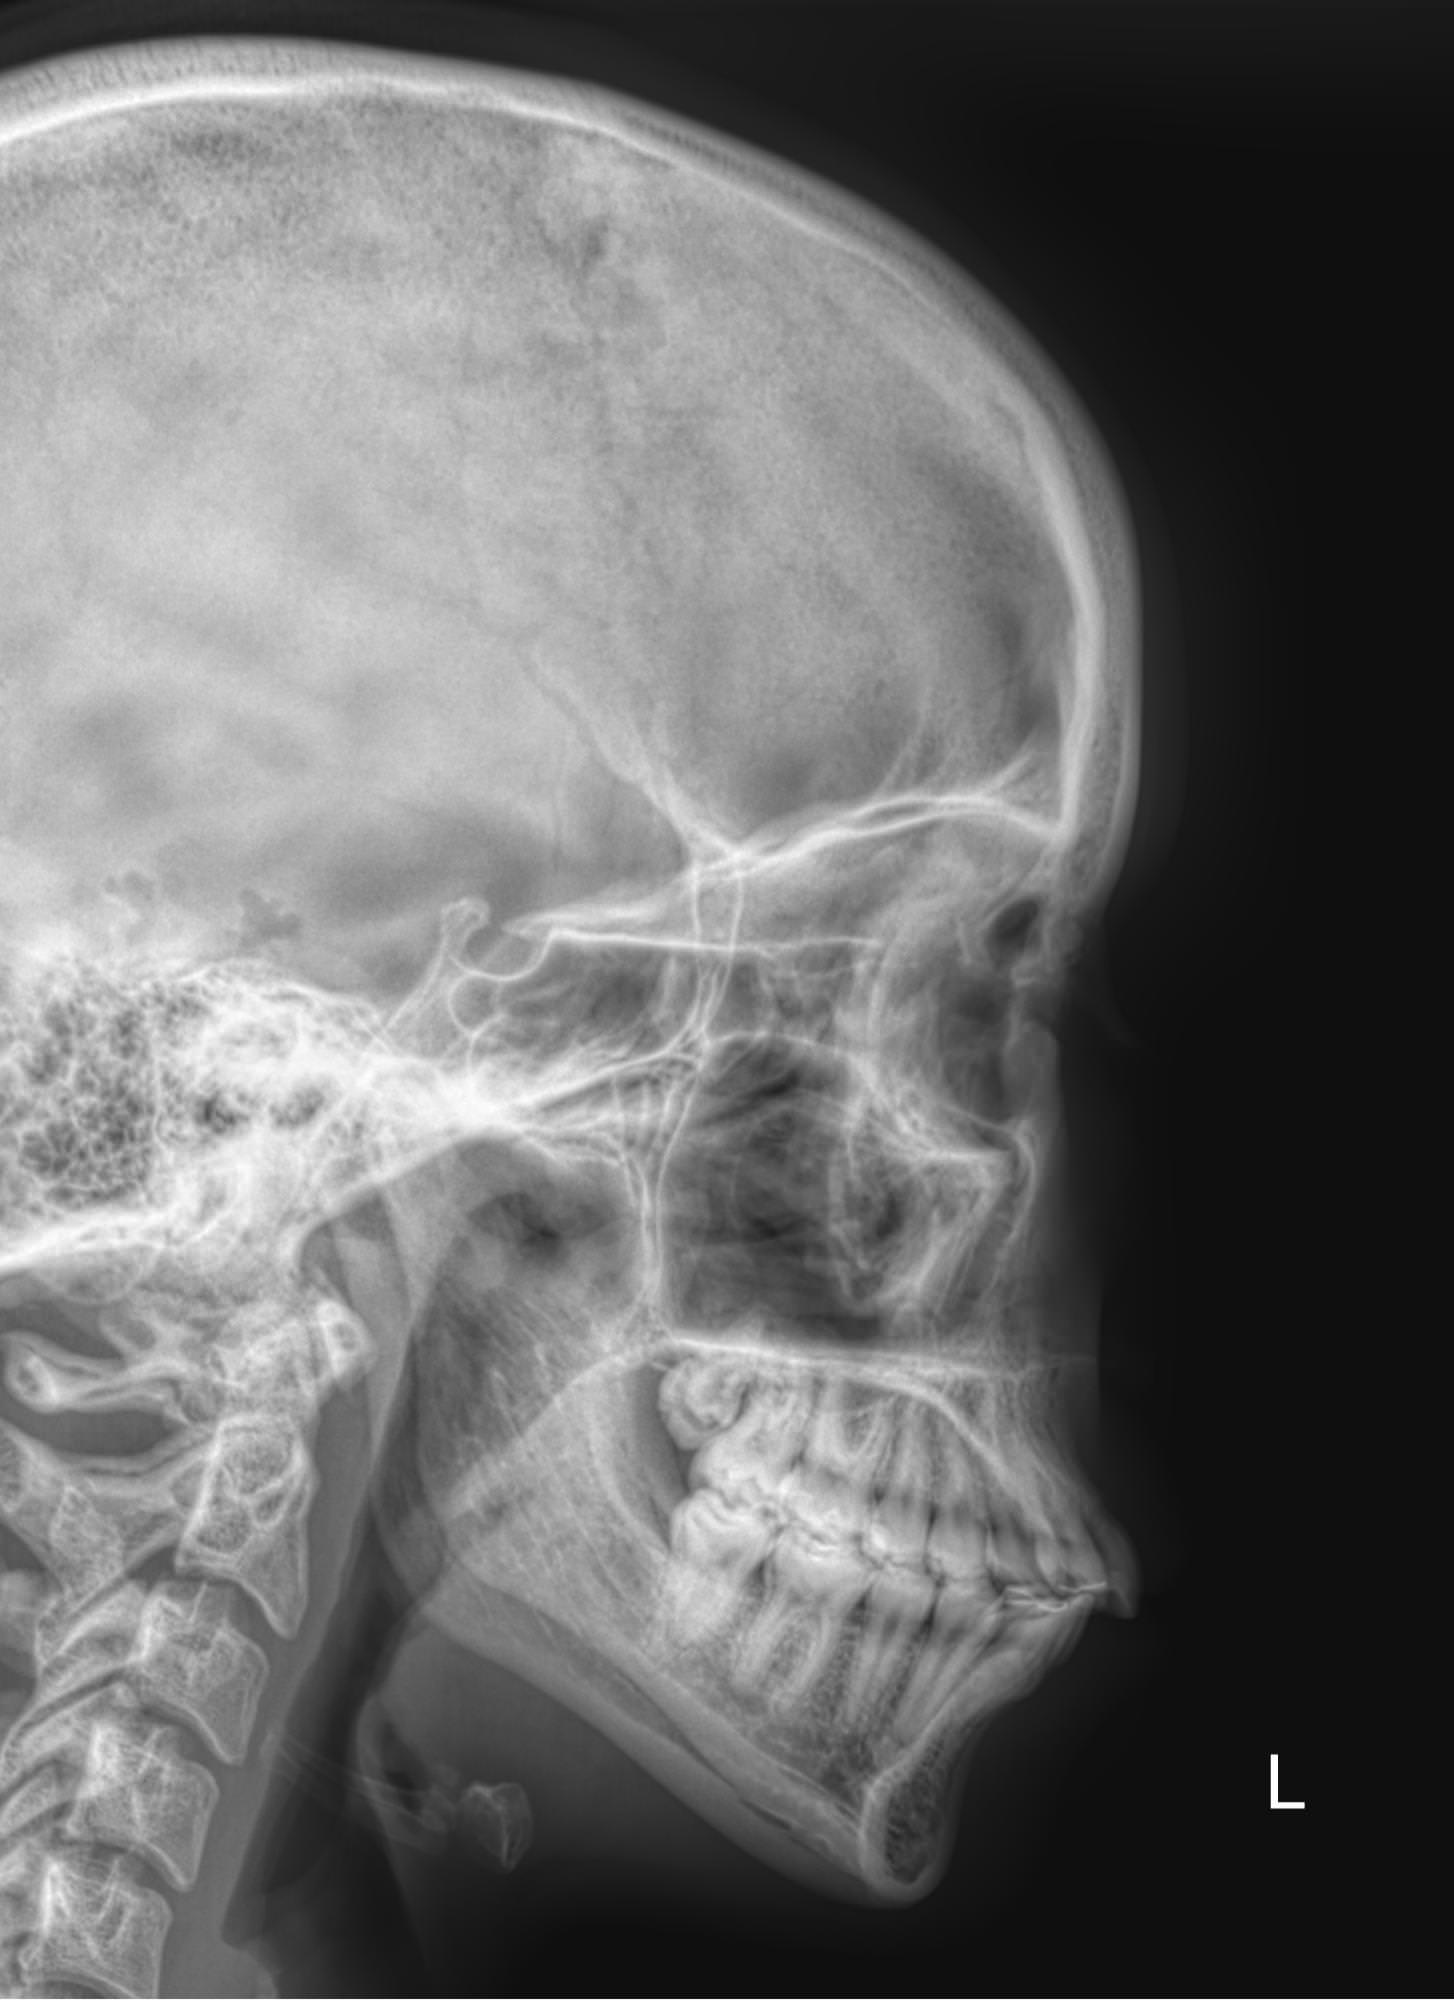

Придаточные или околоносовые пазухи носа ― это система воздухоносных полостей, располагающихся в костях черепа. Пазухи или синусы увлажняют и согревают вдыхаемый воздух, участвуют в формировании голоса, делают кости лица более легкими и смягчают силу удара при травме. К пазухам относятся:

• Гайморовы или верхнечелюстные ― расположены в верхней челюсти;

• Лобные ― в области лба над орбитами;

• Решетчатые ― позади носовых ходов  между орбитами;

• Клиновидные ― в глубине, за решетчатыми.

Что покажет рентген придаточных пазух носа

• Носовая перегородка ― прямая, искривленная, утолщенная;

• Носовые ходы ― свободны, сужены;

• Контур слизистой внутри пазух ―слизистая  обычная, утолщенная, есть рубцевания;

• Внутренние контуры ― четкие, расплывчатые;

• Наличие воздуха ― пневматизация сохранена, снижена;

• Жидкость ― в норме быть не должна, но если она есть, будет виден ее уровень;

• Новообразования;

• Инородные тела.

Правые и левые одноименные пазухи могут поражаться одновременно. Или одна быть здоровой, а другая иметь патологические изменения.